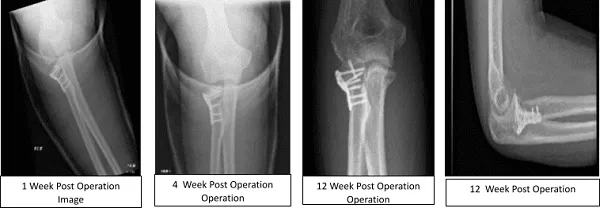

Figure 2. Image of Elbow with 3 cortical screws

A proximal radius plate of appropriate contour was fixed to the radial head using two locking screws. One of the anterior locking screws was passing through the intraarticular fracture site and allowed compression. The head of the radius and the plate was delivered into the wound and aligned with the shaft found to be acceptable and was provisionally fixed with the K-wire.

The plate was fixed to the distal fragment using 3 cortical screws (Figure 2). One more locking screw was passed into the head. No bone gap was found in the fracture site. The patient tolerated the procedure well. The patient was moved to the postoperative care unit in stable condition.

The patient undergo X-ray every week to monitor the progress of the elbow radial fracture. Postsurgical changes at the radial head are noted with satisfactory position of the hardware. In the second week, can notice the Stable postsurgical changes involving the proximal radius.

Third week post saw the repair of a complex fracture of the proximal radius in a good position fixed with plate and screws. After a month, early healing of the surgically treated comminuted radial head fracture is noted.